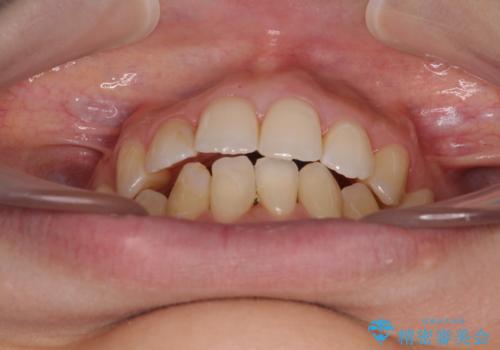

後戻りの再矯正 ワイヤー装置でデコボコと隙間を改善

- 学生時代の抜歯矯正の後戻りが気になり、再矯正を希望して来院された患者様です。

マウスピース矯正は継続する自信がなく、気になるところを短期間で改善したいとのことで、ワイヤー装置にて矯正治療を行うこととしました。

詰め物で隠していた下顎前歯の隙間は、歯軸を改善することで詰め物を除去しても隙間が目立たなくなりました。

まだ改善したいところはありましたが、患者様自身は大変満足されたとのことで、治療を終えることとなりました。